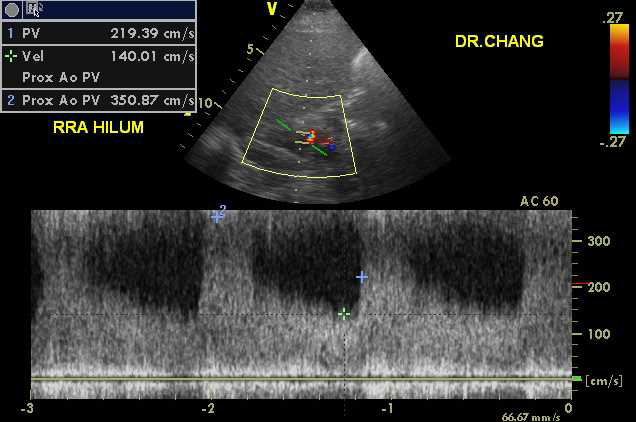

The examination was performed by a registered vascular technologist on a GE Vivid-q ultrasound unit with a M4-S transducer. Gray scale, color and doppler images were obtained from the mid abdominal aorta, the right renal artery and left renal artery. Upon interrogation of the right renal artery, markedly abnormal waveforms and velocities were demonstrated throughout the entire length of the vessel.2 The peak systolic velocity (PSV) was measured at 351cm/sec with an elevated end diastolic velocity of 140cm/sec. The right Renal Aortic Ratio was elevated at 4.3. Of particular interest, color doppler imaging demonstrated a “mosaic” pattern extending from the distal right renal artery into the helium. The left renal artery doppler interrogation was fairly unremarkable with a PSV of 144cm/sec and a Renal Aortic Ratio of 1.78 (Figure 1-3).

Figure 7 Color and Doppler images of RRA FMD.

Figure 8 Color and Doppler images of RRA FMD.

Figure 9 Color and Doppler images of RRA FMD.